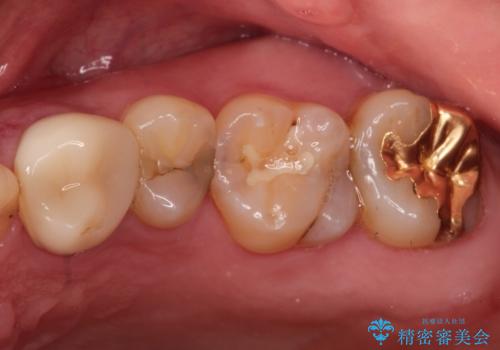

- 定期健診にて虫歯が見つかった患者さんです。他院で保険治療(CR、プラスチック)したところとまだ処置されていないところが虫歯になっていました。

セラミックインレーで治療しました。

以前保険治療で治したところが再び虫歯になっていました。保険治療で使用される材料は主にプラスチックなので必ず劣化がおきます。再治療のリスクを減らすために、セラッミックインレーで治療を行いました。セラミックインレーには劣化がほとんどありません。当院ではシリコンで型取りを行っているので、適合が良い被せものが出来き再治療のリスクを減らすことが出来ます。